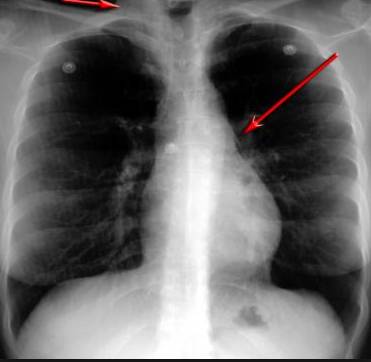

并且,因為呼吸系統(tǒng)結(jié)構(gòu)復(fù)雜,在體檢時醫(yī)生很難通過一種檢測手段,判定早期患者的病情。

把整個肺部看得清清楚楚!

使用這臺掃描儀,將直接把器官變成3D圖形!細(xì)微的毛細(xì)血管,幾毫米大的肺泡和支氣管,都將能看的一清二楚!

你的每一個氣泡,每一段支氣管,哪兒有病變都清清楚楚的將展示在醫(yī)生面前!

也就是說在一切都還沒開始惡化前,把這些有問題的器官組織都暴露的一清二楚:

不同于CT掃描,需要從同一角度,拍下無數(shù)張器官二維圖,從而搭建3D器官結(jié)構(gòu)圖那般費時費力。

沒有這項新技術(shù),醫(yī)生在做體檢的時候,很難通過一種測試斷定一個人是否有呼吸系統(tǒng)疾病。

可是現(xiàn)在他們不但能看到整個肺部的3維結(jié)構(gòu)圖。還能看到空氣進入人體后的所有微小變動!